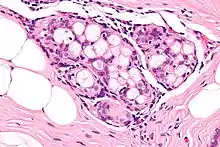

Collagenous spherulosis is characterized by a tubular/cribriform architecture with intratubular eosinophilic material that classically is arranged like the spokes of a wheel ("radial spikes"). There is usually no mitotic activity, and two cells populations (epithelial & myoepithelial) are present, like in benign breast glands.

The lesions are typically small (less than 50 spherules per lesion, less than 100 micrometers in size) and may be multifocal.

High mag.